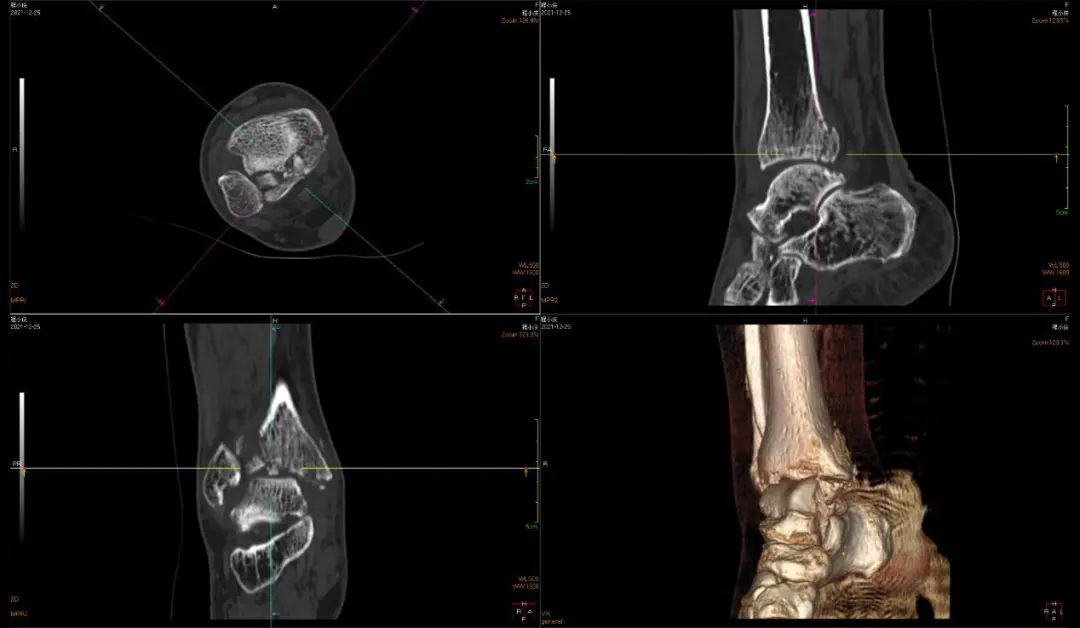

CT检查是多层断面成像,对于细微骨折、复杂部位骨折是强项

CT全称为计算机X线断层扫描,是一种常用的影像学检查方法。先由X线照射一定厚度的人体组织,然后通过接收器接收穿过该组织的X线,并将其转化为电信号和数字信号,最后通过计算机处理形成CT图像,具有较高的分辨率。CT检查可以从任意方向对图像进行二维重建和三维立体重建,避免骨头前后重叠造成的误解影像,并且能很好显示骨折线的走行、累及关节面情况,能够更好地评价骨折的严重程度。因此,对于某些特殊部位的细微骨折、需要进一步观察骨折线累及关节面情况、评估骨折严重程度的骨折,则需要进一步CT检查。